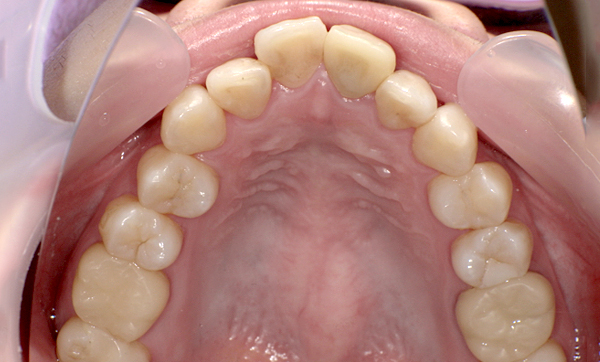

症例_011 「出っ歯」症例

治療期間:7ヶ月金額:30万円+税20代女性出っ歯捻転歯上の前歯だけ

| Before | After |

|---|---|

症例_010 「出っ歯」症例